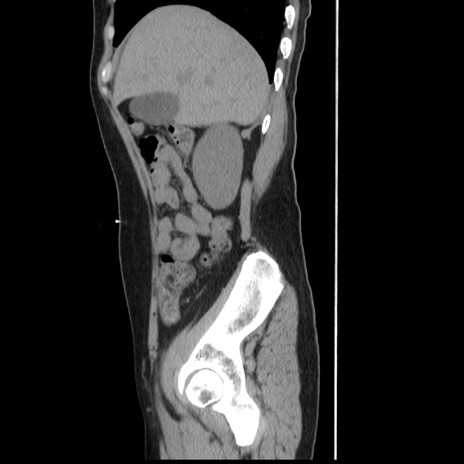

症例10(矢状断像)

【症例】 50歳代女性

【主訴】 腹痛

【現病歴】前日生レバーを食べた。今朝に排便あり。 昼前に突然発症の腹痛を生じ、当院救急外来を受診した。

【既往歴】 子宮筋腫にてで子宮全摘後

【身体所見】 意識清明、腹部:平坦、軟、下腹部やや左を中心に圧痛・反跳痛あり、筋性防御あり

【データ】WBC 7800、CRP 0.07